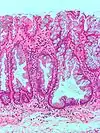

| Hyperplastic polyp of the stomach | Stomach | Elongated, tortuous, and cystic foveolae separated by edematous and inflamed stroma.[4] | ![]() |

Gastric hyperplastic polyposis | |